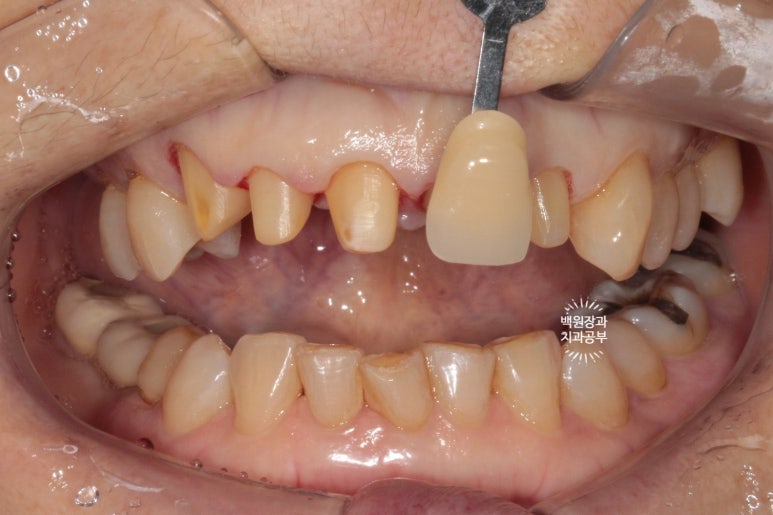

그랬지만, 이번에는 조금 어둡기도 하고, 송곳니가 길어보여서 만족스럽지 않다 말씀하신 환자분...

넵 그래도 수정 해드려야지요.

이렇게해서 두 번 수정한 앞니 지르코니아 크라운입니다.

처음에 비해 훨씬 가지런해지고 여성스러운 모양을 가진 치아로 완성되었네요!